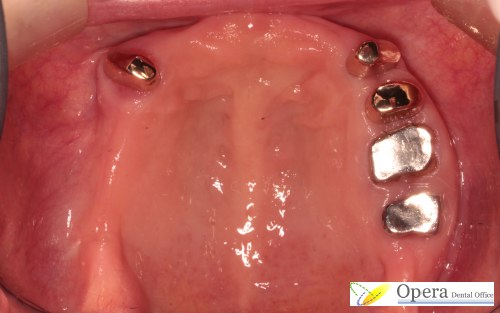

義歯装着の図です。

下あごの歯は割としっかりしていて、今後なくなる雰囲気はありませんでした。

そこで、歯を被せ物にせず、義歯だけを作りました。

この義歯はしっかりとはまって、かつ、バネが見えません。ミラクルデンチャーと言います。

残っている歯がかなりしっかりしているならば、このミラクルデンチャーはおすすめできると思います。当医院では385,000円(税込)で行なっております。